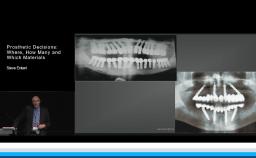

This presentation highlights the critical considerations to treat posterior edentulous spaces with implant restorations from one of the most experienced clinicians in the field, Dr. Morton. With a series of clinical cases, he explains various factors influencing the treatment planning with posterior implant prostheses including implant and prosthetic designs, abutment and prosthetic materials, abutment connections, inter-arch space considerations, and nature of opposing dentition. The presentation highlights the management of clinical situations with adequate, inadequate, and excessive interocclusal spaces as well as available bone volume with careful selection of implant and prosthetic designs. The importance of digital implant planning and digital prosthetic designs for posterior restorations is emphasized.

- explain different implant treatment strategies in managing posterior edentulous spaces

- discuss prosthetic designs and material considerations for posterior implant restorations